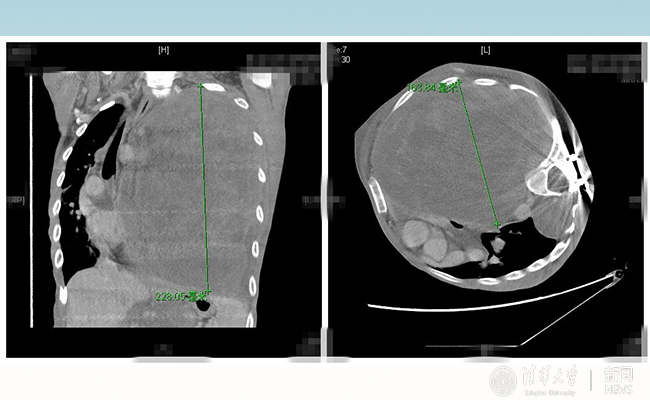

开云长庚医院多学科助力胸外科手术,成功帮28岁的患者“小飞”切除巨型神经纤维瘤,帮助重病的患者重生。